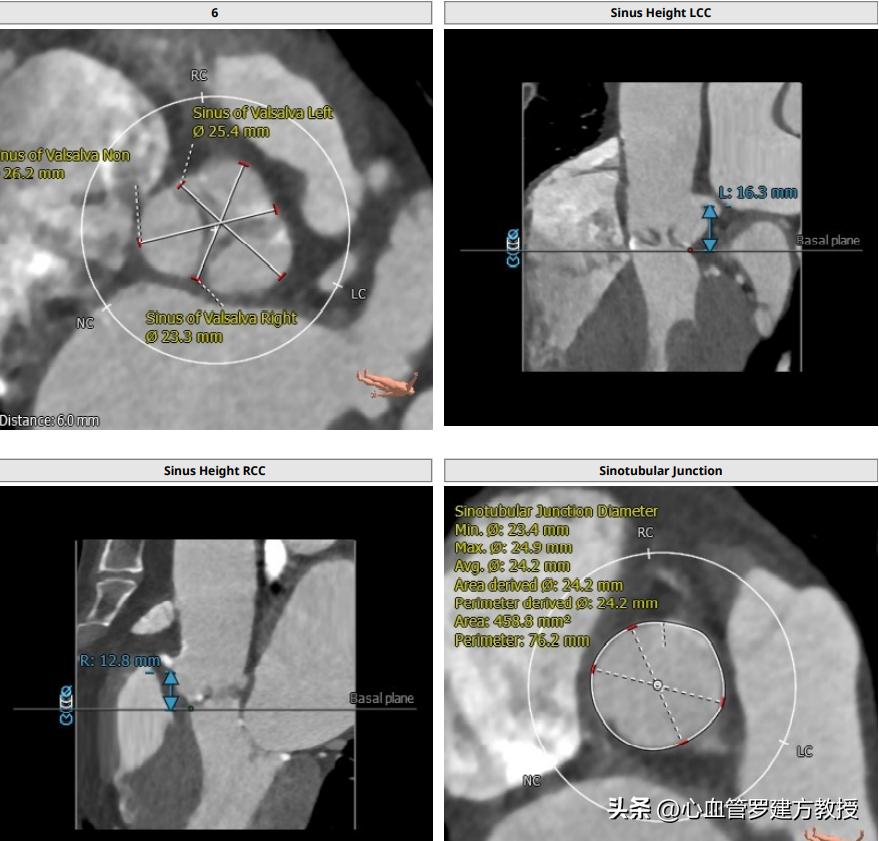

病人女,64岁,2018年在广东省人民医院行TAVR手术,三叶瓣,轻度钙化,瓣环20.5,Lvot 20.6,左右冠高度尚可,STJ 24.2,窦部长短径分别为26.3及23.3,窦部空间相对较小,结合术中球扩结果,瓣膜冠脉风险不高,遂植入VenusA 26号瓣膜。